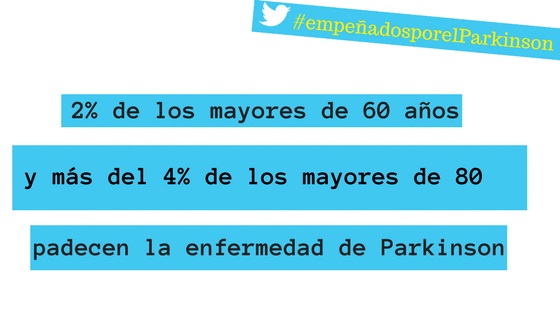

Con motivo de la conmemoración, el 11 de abril, del Día Mundial del Parkinson, la Sociedad Española de Neurología ha colaborado con Ippok Comunidad Sanitaria (la Comunidad de Diario Médico y Correo Farmacéutico) en la elaboración de un Quiz Interactivo sobre esta enfermedad.

Con motivo de la conmemoración, el 11 de abril, del Día Mundial del Parkinson, la Sociedad Española de Neurología ha colaborado con Ippok Comunidad Sanitaria (la Comunidad de Diario Médico y Correo Farmacéutico) en la elaboración de un Quiz Interactivo sobre esta enfermedad.

Si es usuario de Ippok puede acceder al mismo en el siguiente enlace: http://www.ippok.com/quiz/evidencias-de-la-practica-clinica-en-la-enfermedad-del-parkinson-ponte-al-dia